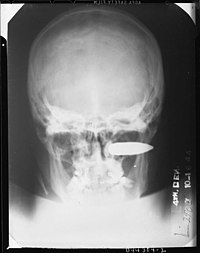

Depiction of a gunshot wound of the brain. (WC/National Library of Medicine)

X-rays are useful for locating bullets. (WC)

• Thus, all projectiles are recovered from a body... and it is routine to X-ray all gunshot victims.